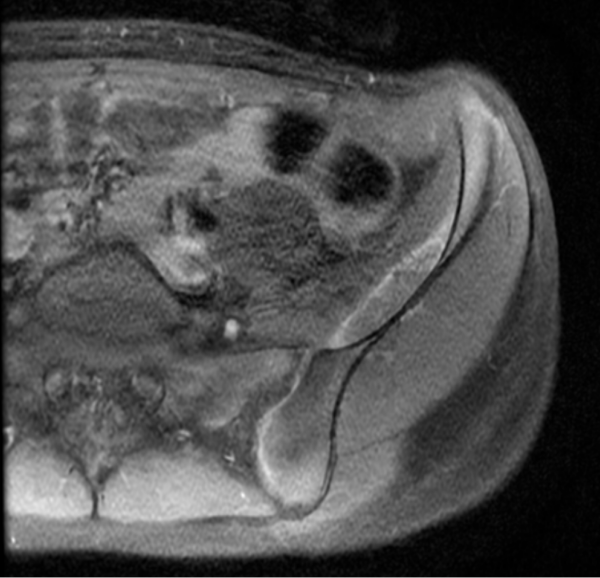

RM de cadera izquierda, secuencia PD TSE FS axial (Imagen 1) y sagital (Imagen 2). Se observa una imagen lentiforme subperióstica ilíaca de alta señal, bien delimitada, con un nivel líquido-líquido.

Secuencias de pelvis axial, T1 FSE, sin (Imagen 4) y con contraste (Imagen 5). La lesión presenta señal alta, levemente heterogénea, con nivel líquido-líquido. No demuestra realce significativo con el contraste endovenoso.